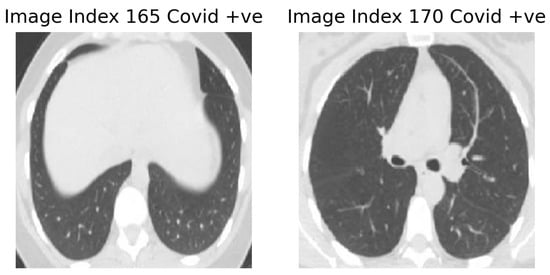

We have also stacked the different combinations of these three models for the improvement of the model for the prediction of COVID-19. Table 2 reflects the outcomes observed for different combinations of the used models. After analyzing Table 2, it can be said that the ensembling of models (any combination) produces better recognition accuracy than the individual one. The best recognition accuracy of 98.79% was observed when all the three models were ensembled. For this model, the observed classification accuracy, precision, recall, and F 1 -score are 98.79%, 0.99, 0.99, and 0.99, respectively. It can be seen from Table 1 that Xception does not perform well considering all the metrics when compared to the other two base models, namely VGG-16 and ResNet50. However, the stacking ensemble consisting of all three base models outperforms all other combinations. We used a fully connected neural network as a meta-learner to provide flexibility to the stacked model and decrease the generalization error. Thus, the neural network combines the predictions obtained from all the base models in such a way that the performance of the overall model improves. The neural network is tuned so that it can ignore the wrong predictions made by the base models and utilizes only those predictions that help improve the classification score. Different CNN models commit errors on different samples; thus, aggregating those together helps to achieve a better accuracy on the test set. Image index 165 belongs to a test set and was originally a COVID image. It is misclassified by VGG-16 as a non-COVID image but properly classified by ResNet50 and Xception. It is also misclassified by both VGG-16+ResNet50 and VGG-16+Xception combinations, but in the stacked model, it is properly classified. Similarly, image index 170 belongs to the test set and is originally a COVID +ve CT-scan, which is misclassified by Xception but accurately recognized by VGG-16 and ResNet50. As all three models are included in the final ensemble architecture, it gets correctly classified by the stacking ensemble model. The aforementioned images can be seen in Figure 5. The complete test set contains 497 samples. The pronounced difference in the performance of the said models on the test set can be visualized from confusion matrices shown in Figure 6. In the final confusion matrix of the stacking ensemble model that can be seen in Figure 7, only four COVID +ve images are incorrectly classified as non-COVID, and two non-COVID samples are recognized as COVID samples. This can be considered as a significant improvement compared to other models.

Figure 5. Images misclassified by the base models but accurately recognized by the proposed ensemble framework.